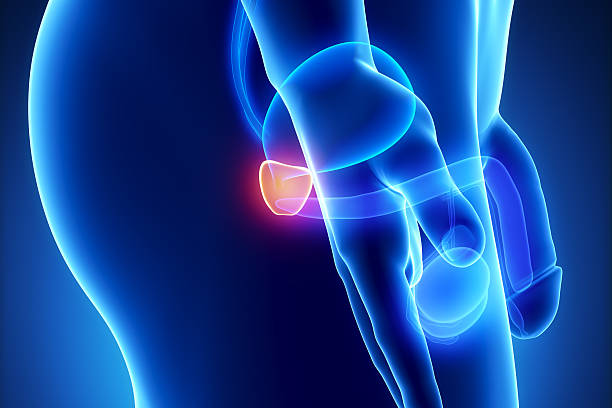

전립선 저적술은 전립선의 크기를 줄이는 방법 중 하나로, 저온열을 이용하여 전립선 조직을 소실시키는 방법입니다. 전립선 비대증의 정도에 따라 다양한 방법으로 시행됩니다.

전립선 저적술은 일반적으로 경증에서 중등도의 증상을 가진 환자에게 시행되며, 수술 후 회복 기간이 짧아 일상생활로 빠르게 복귀할 수 있습니다. 단, 저적술을 시행하는 동안 일시적으로 소변 장애가 생길 수 있습니다.